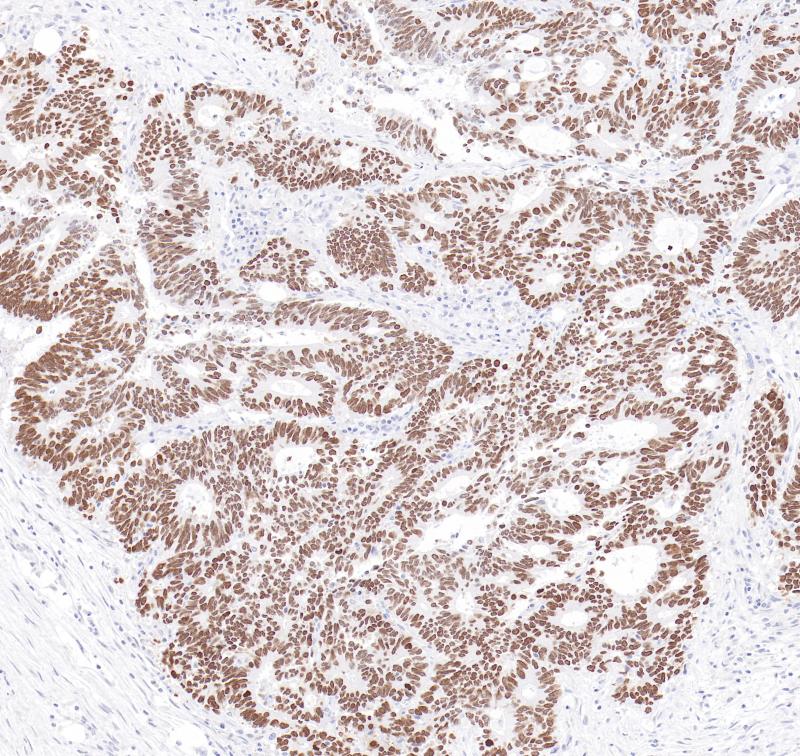

配对同源异型盒蛋白2B(PHOX2B),编码一种高度保守的转录因子同源域蛋白,最初在神经母细胞瘤(NB)细胞株中被发现。PHOX2B作为转录因子在外周交感神经系统中具有高度的特异性,尤其是神经元和嗜铬细胞的分化过程中起关键作用。PHOX2B在神经母细胞瘤(NB)组织中具有高度的敏感性和特异性。

阳性对照

神经母细胞瘤

亚细胞定位

细胞核